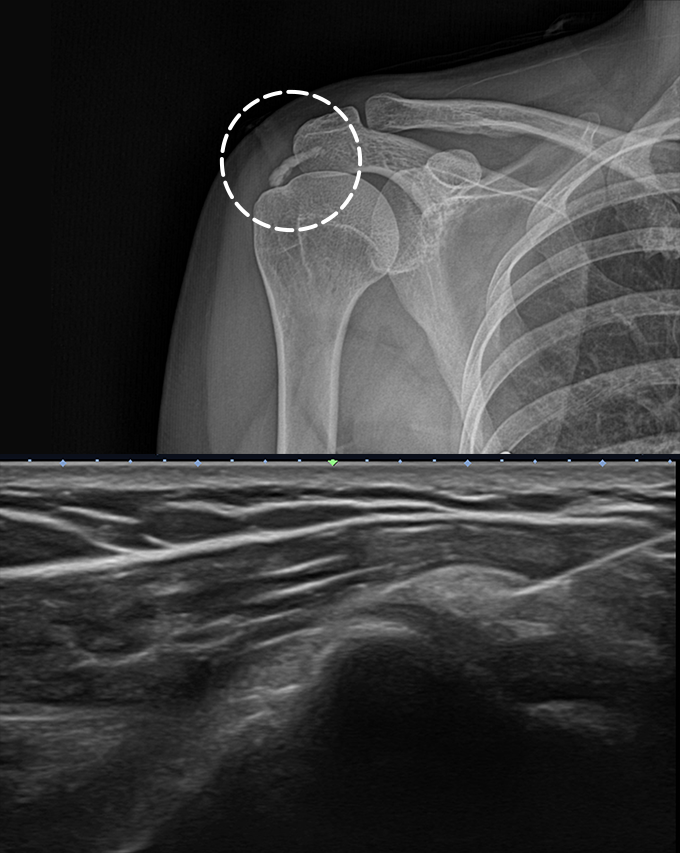

초음파 유도하 석회제거술

수술 없이 석회를 직접 제거하는 시술

석회성건염 환자를 위한 비수술적 치료법으로, 초음파로 석회의 정확한 위치와

크기를 파악한 후 얇은 바늘로 석회를 직접 제거하는 시술입니다.

프로정형외과에서는 20년 이상의 풍부한 어깨치료 경험을 가진 의료진이 초음파로

정확한 석회 위치를 파악하고 정교하게 시술을 진행합니다.